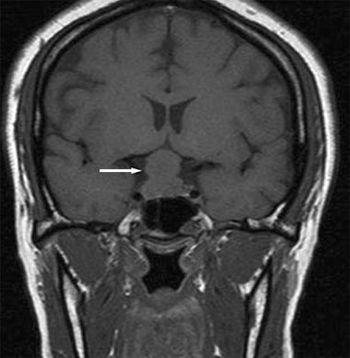

During circumcision, a newborn is noted to have continuous dribbling of urine from his meatus and stool from his anus. After several minutes of observation, the urinary stream appears weak and remains a constant trickle. The baby boy was born at term via an uncomplicated spontaneous vaginal delivery. He was treated in the neonatal ICU for hypoglycemia. A radiograph of his pelvis is shown.